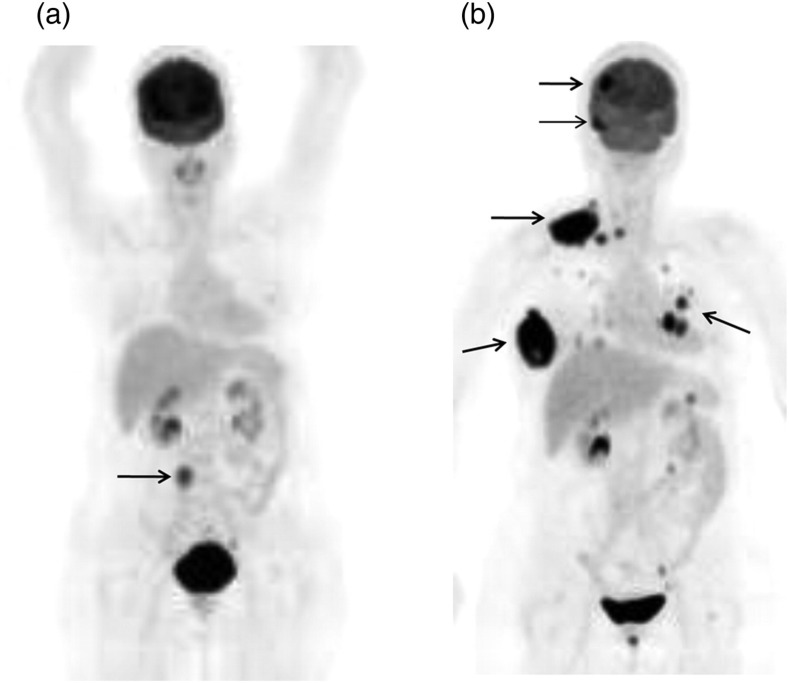

宫颈恶性黑色素瘤是一种罕见的皮肤外黑色素瘤,其发展积极,预后黯淡。据我们所知,之前没有发表的报告讨论过18F-FDG正电子发射断层扫描/计算机断层扫描(PET/CT)在治疗这种疾病中的作用。我们的病例研究涉及一名66岁的宫颈恶性黑色素瘤妇女。患者接受了PET/CT检查,发现了MRI未检测到的转移和病变。连续PET/CT显示,该疾病最初局限于骨盆,但随后转移到腹部主动脉旁淋巴结,随后广泛转移到脑、肺、乳房、锁骨上、颈部和其他腹部淋巴结,随访6个月。PET/CT用于补充传统的解剖成像方式,为全身筛查提供了一种新的方式。不确定病变的代谢活动可视化可能有助于这种罕见疾病患者的分期、再分期、治疗计划和预后预测。

Malignant melanoma of the uterine cervix is a rare extracutaneous melanoma which develops aggressively and is associated with a bleak prognosis. To our knowledge, no prior published reports have discussed the role of 18F-FDG positron emission tomography/computed tomography (PET/CT) in managing this disease. Our case study involved a 66-year-old woman with a malignant melanoma of the uterine cervix. The patient received PET/CT that identified metastases and lesions which had not been detected from her MRI. Serial PET/CT elucidated that the disease was initially limited to the pelvis, but then metastasized to the abdominal para-aortic lymph nodes, followed by extensive metastases to the brain, lungs, breast, supraclavicular, neck, and other abdominal lymph nodes, as observed at 6-month follow-up. PET/CT was used to complement conventional anatomic imaging modalities, and provided a novel modality for whole body screening. Visualization of the metabolic activity of indeterminate lesions may help in staging, re-staging, treatment planning, and prognostic prediction for patients with this rare disease.